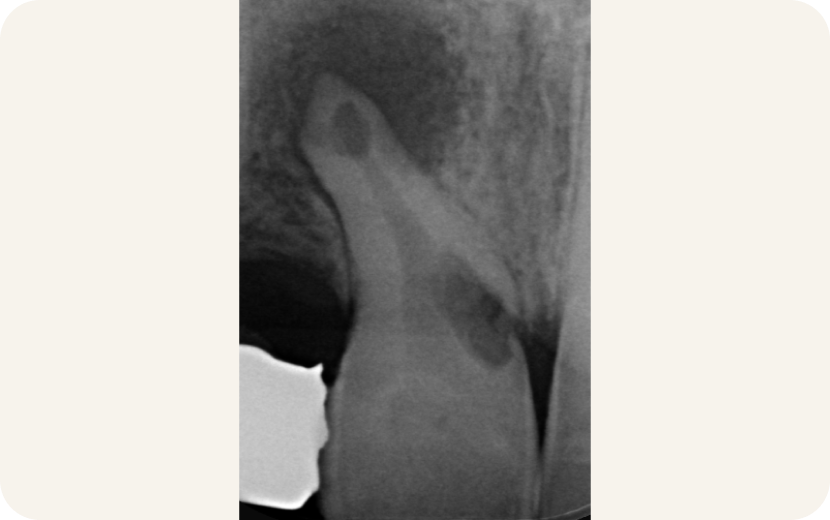

La résorption interne dentaire est un processus pathologique où des cellules situées à l’intérieur de la dent décomposent et absorbent progressivement la dentine depuis la chambre pulpaire ou le canal radiculaire. Différents facteurs peuvent en être à l’origine, comme une infection, un traumatisme ou certaines interventions dentaires. Si elle n’est pas traitée, cette atteinte entraîne une perte progressive de structure et peut aller jusqu’à la disparition de la dent.

La résorption externe dentaire, quant à elle, survient lorsque les cellules situées à l’extérieur attaquent la surface radiculaire. Elle peut être liée à un traumatisme, à une infection parodontale, à des pressions trop fortes sur la dent ou à une inflammation. Cette forme se manifeste souvent par une perte de la crête osseuse ou par des changements visibles de la racine sur les radiographies. Sans intervention, la dent peut également être compromise.